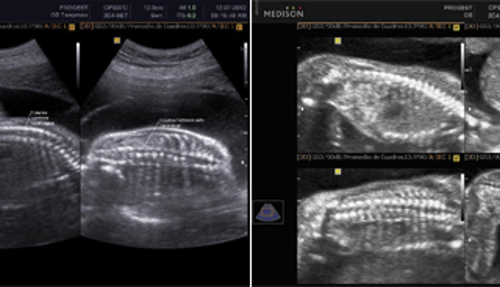

También llamada Ecografía de Tercer Nivel, comprende de un examen detallado de las estructuras anatómicas fetales, así como la valoración del crecimiento y de los marcadores ecográficos de alteraciones cromosómicas del segundo trimestre.

Es la ecografía a nivel obstétrico más importante ya que sirve para diagnosticar y comprobar la existencia de todos los órganos fetales y posibles malformaciones en el feto, y la etapa apropiada para tomarla es de la semana 20 a la 24 de gestación.